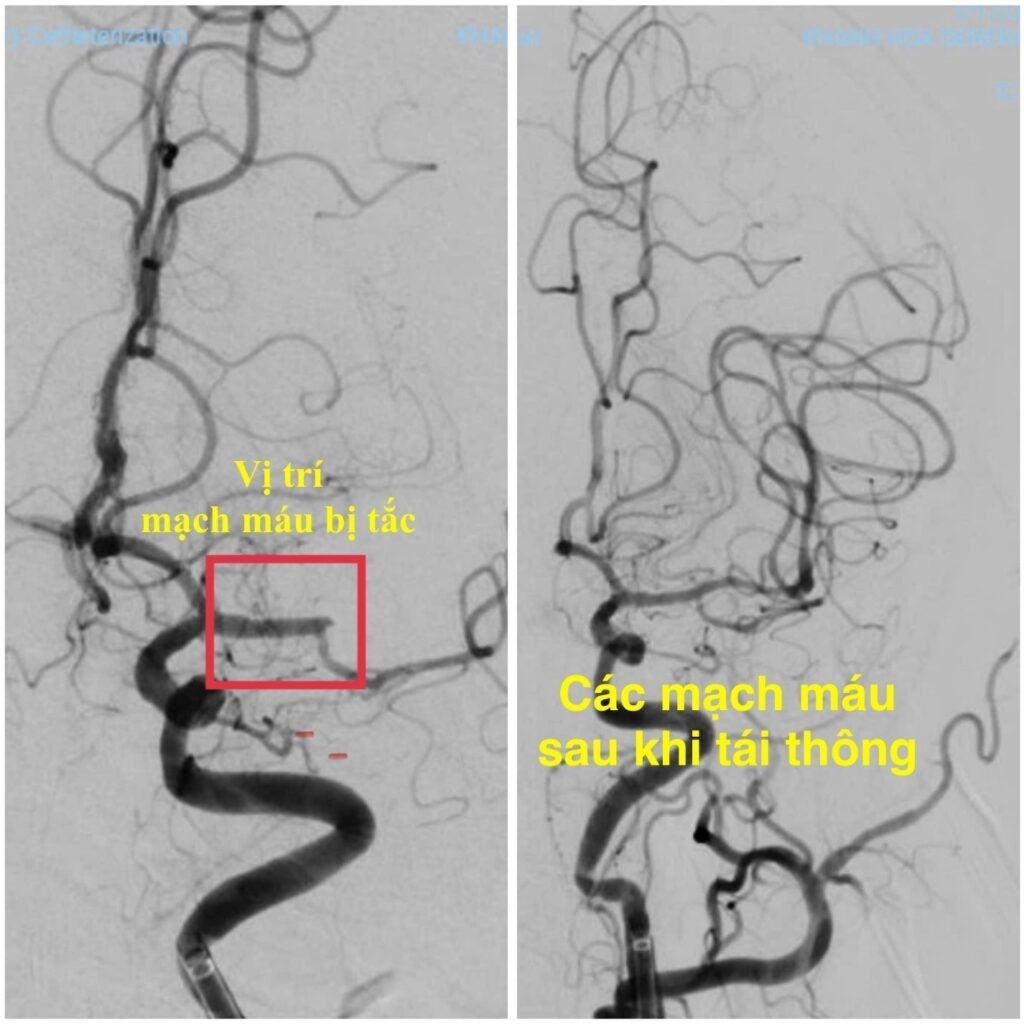

Ngay trong đêm, ê-kíp can thiệp mạch não Khoa Đột quỵ đã nhanh chóng tiến hành can thiệp lấy huyết khối và tái thông hoàn toàn động mạch não giữa trái bằng hệ thống máy DSA. Thủ thuật được thực hiện khẩn trương, chính xác, đảm bảo an toàn cho người bệnh.

Cấp cứu đột quỵ lấy huyết khối cơ học thời gian vàng đột quỵ can thiệp mạch não Bệnh viện Đa khoa Khánh Hòa nhồi máu não cấp - Ảnh BVCC

Chỉ sau 24 giờ can thiệp, bệnh nhân cải thiện ngoạn mục, tỉnh táo, giao tiếp trở lại bình thường, chỉ còn yếu nhẹ nửa người phải với sức cơ 4/5. Kết quả CT sọ não kiểm tra cho thấy tổn thương nhỏ, khu trú vùng vành tia cũ, không ghi nhận biến chứng xuất huyết. Sau vài ngày bệnh nhân phục hồi gần như hoàn toàn.

Hình ảnh mạch máu não trước và sau can thiệp - Ảnh BVCC